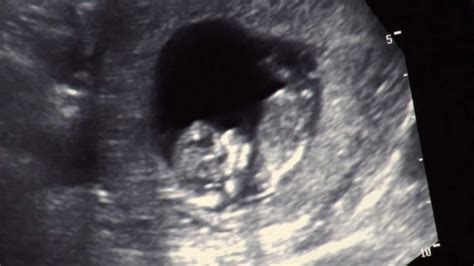

Joi, 30 mai, vedeta și-a luat rămas-bun de la telespectatori, șefi și colegi, în lacrimi. Sandra Stoicescu (43 de ani) este însărcinată în aproape 8 luni și a aflat recent că sarcina ei a ajuns la 31 de săptămâni și este mai avansată decât știa. După ultima ecografie pe care a făcut-o, medicul i-a spus prezentatoarei că va naște undeva la mijlocul lunii iulie, deși ea știa că fericitul eveniment se va petrece în august.

"Surpriza este că sunt de fapt însărcinată în 31 de săptămâni și am aflat acest lucru la ecografia recentă. Acum, se explică dimensiunea burticii. Mă voi întoarce pe la alegerile prezidențiale (n.r noiembrie-decembrie) dacă mă primiți. Abia aștept acele nopți în care nu o să dorm, pentru că trebuie să o veghez pe cea mică."